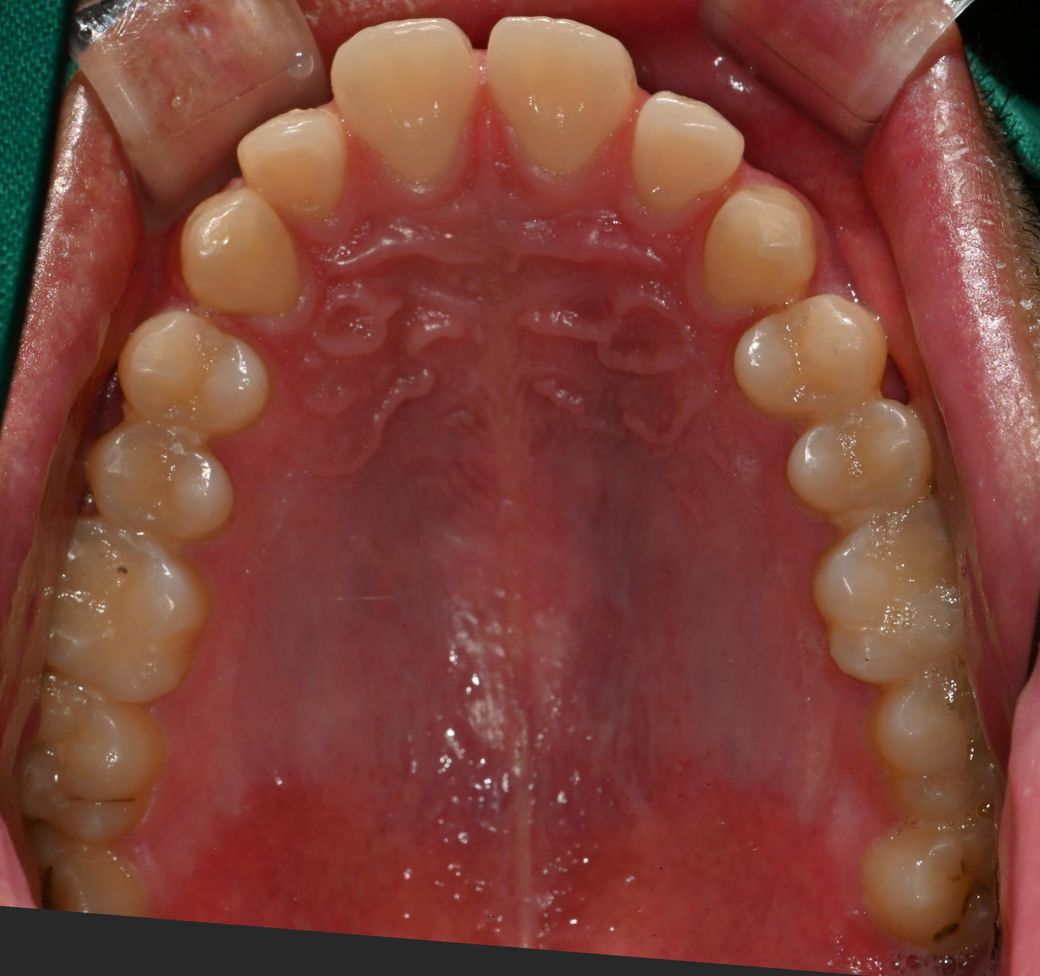

오늘 치과 2곳에서 원장님이 어금니 인레이가 필요한 충치가 있다고 하셨습니다. 위 사진에서 조금 긁어보시더니 C1 C2충치가 각각 있다는데, 어금니의경우 상아질에 접근한 충치의 범위가 커 보인다고 인레이를 하는게 좋겠다 하십니다. 특히 어금니는 씹는면 음영상 내부우식쪽으로 간거같다 하시는데 그정도로 제 충치상황이 악화된건가요? 파봐야 안다고하시든데 통증은 전혀 없지만 인레이 중 신경치료가능성이있나요?

• 1번 째 사진